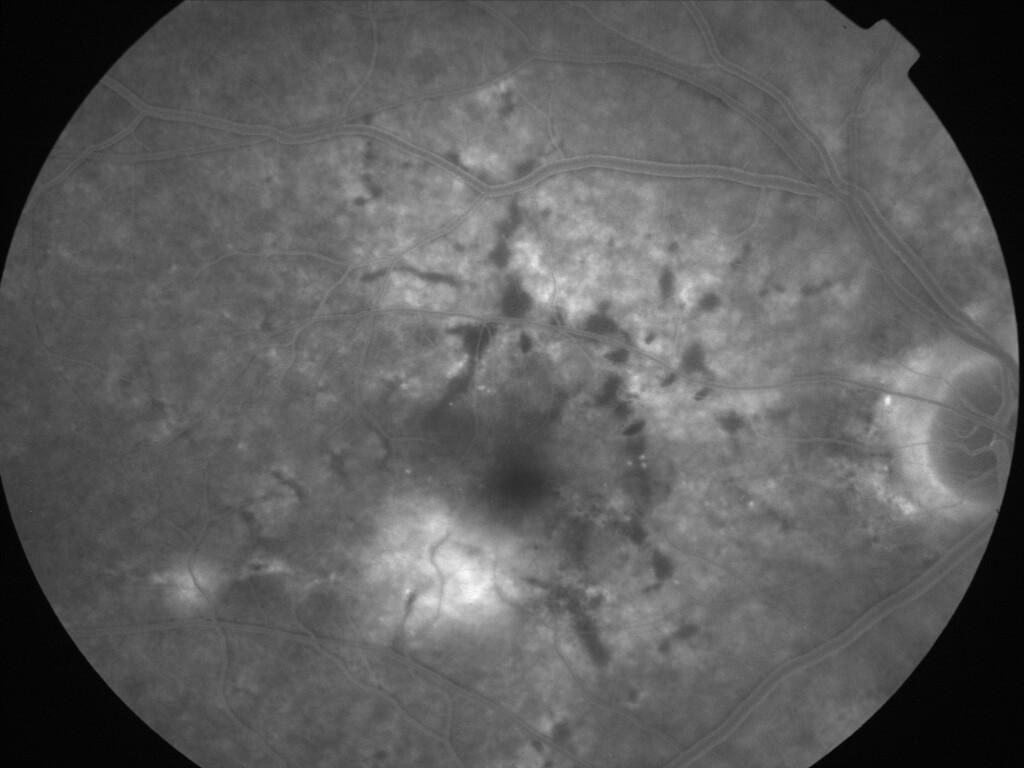

ASSOCIATION STRIES ANGIOIDES ET DYSROPHIE MACULAIRE RETICULEE

NEOVASCULARISATION